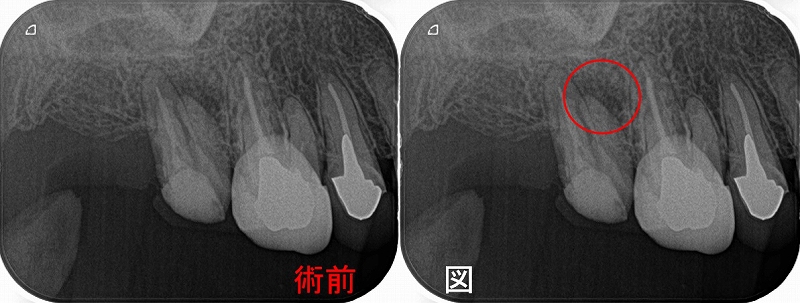

患者さんは50代女性 2013年に私がセラミッククラウンを3本入れさせてもらった前歯なのですが、

半年前からプチっと小さなニキビのような膿が出てきた。

レントゲン

レントゲンを撮っても、原因歯が特定できず

CTを撮らせてもらいましたが、はっきり特定できず・・・

ただ、フィステルがあるということは出口からたどれば原因部分を特定できるので、

患者さんに膿が出ている間に外科的歯内療法を行いましょうと説明